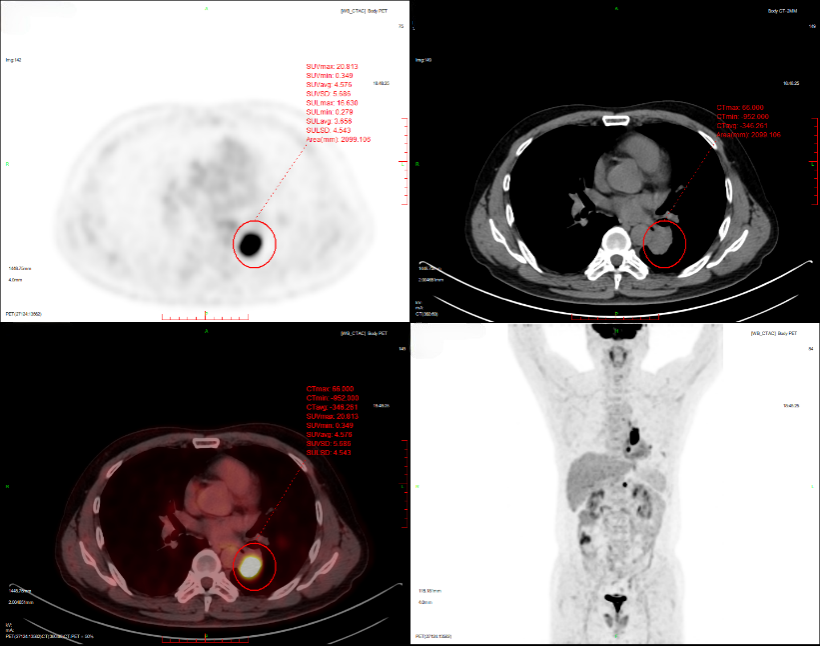

2024-11-26 PET-CT进一步评估:左肺下叶背段近肺门处类圆形分叶状肿块(约32*28mm),FDG代谢异常增高;纵隔内4L组、左下肺门处、左侧膈肌脚内侧见稍大淋巴结FDG代谢增高,左肺内及胸膜下散在多发结节影,FDG代谢不同程度增高,考虑左肺下叶肺癌伴左肺及胸膜多发转移、多发淋巴结转移。

基因检测:检出I类变异LINC00707(Intergenic)-ALK(Exon20-29)。

左肺恶性肿瘤(左肺腺癌IVA期,cT2aN2M1a,胸膜),LINC00707-ALK融合,TPS 0%,PS评分1分。

2024年12月11日,予洛拉替尼100mg QD治疗。

治疗5个月后(2025-05-07):复查CT显示左肺病灶显著缩小,达到PR,肺内结节明显吸收。

截至目前,PFS已超过10个月,病情持续稳定。